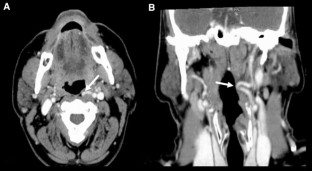

Fig. 1

Simões, J., Miguéis, J. & Miguéis, A. A pulsatile pharyngeal wall: case report and clinical relevance. Surg Radiol Anat 39, 819–820 (2017). https://doi.org/10.1007/s00276-016-1809-4

• Internal Carotid Artery

• Pharyngeal Wall

• Posterior Pharyngeal Wall

• Foreign Body Sensation

• Left Internal Carotid Artery